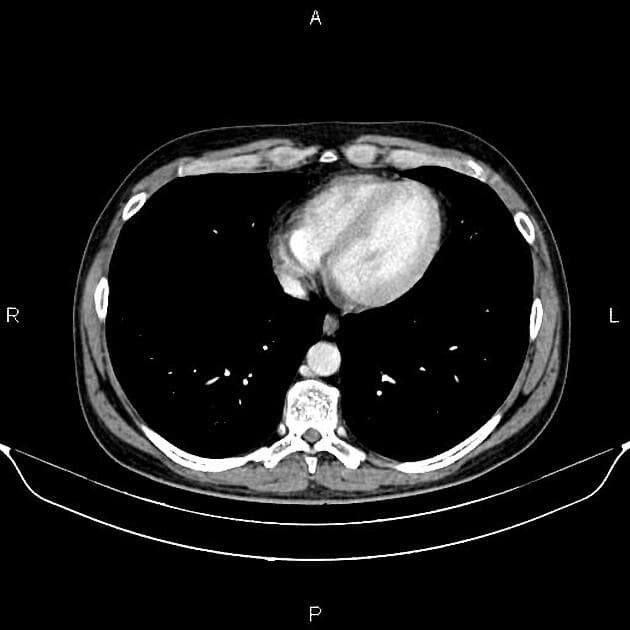

Axial C+ arterial phase

- Tụy (pancreas) bị giãn to, chủ yếu ở vùng đuôi tụy, kèm theo phù mô kẽ (edema) và tăng quang đồng đều (uniform contrast enhancement).

- Không thấy hình ảnh vùng hoại tử (necrotic areas).

- Có xâm nhiễm mỡ (fat infiltration) và dịch quanh tụy (fluid collection), lan vào bao mạc nối (omental bursa), rãnh cạnh đại tràng trái (left paracolic gutter) và vùng hạ vị (hypogastric region).

- Không thấy sỏi túi mật (gallstones).

- Có lượng nhỏ tràn dịch màng phổi trái (small amount of left-sided pleural effusion).

- Xẹp phổi từng phần (partial collapse) ở vùng đáy phổi hai bên, nặng hơn bên trái.

Hình ảnh học, xét nghiệm máu và thăm khám lâm sàng phù hợp với (consistent with) chẩn đoán viêm tụy cấp (acute pancreatitis), độ Balthazar E, điểm CTSI = 4 (mức độ trung bình).

Các hình ảnh chụp cho thấy viêm tụy cấp thể phù nề kẽ, đặc trưng bởi tình trạng giãn to tụy, phù mô kẽ và tăng quang đồng đều, chủ yếu ở đuôi tụy. Dấu hiệu xâm nhiễm mỡ quanh tụy và dịch tích tụ lan vào bao mạc nối, rãnh cạnh đại tràng trái và vùng hạ vị hỗ trợ chẩn đoán viêm tụy cấp mức độ trung bình. Việc không thấy vùng hoại tử giúp loại trừ thể viêm tụy hoại tử. Tràn dịch màng phổi trái ít và xẹp phổi từng phần ở đáy phổi hai bên, nặng hơn bên trái, là các phát hiện thứ phát phổ biến do dịch viêm và kích thích cơ hoành. Không phát hiện sỏi mật, nguyên nhân có thể không do mật. Điểm CTSI = 4 (độ Balthazar E) xác nhận mức độ bệnh trung bình, thường cần nhập viện và điều trị hỗ trợ, tiên lượng tốt hơn so với các thể hoại tử.